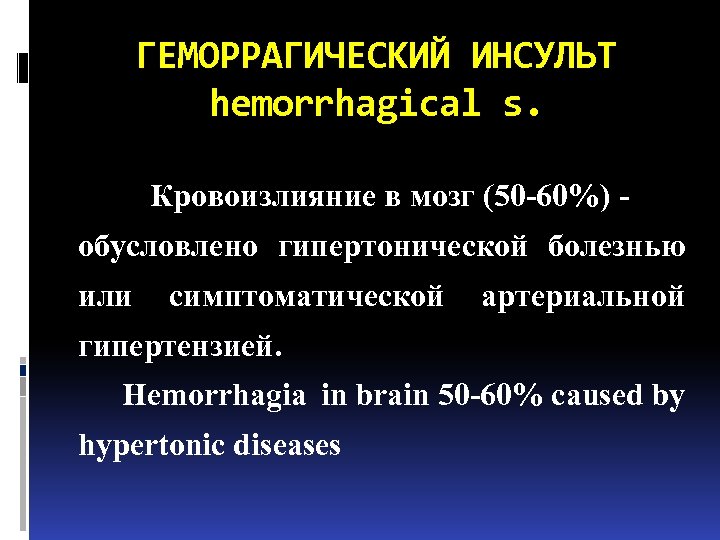

ГЕМОРРАГИЧЕСКИЙ ИНСУЛЬТ hemorrhagical s. Кровоизлияние в мозг (50 -60%) - обусловлено гипертонической болезнью или симптоматической артериальной гипертензией. Hemorrhagia in brain 50 -60% caused by hypertonic diseases

ГЕМОРРАГИЧЕСКИЙ ИНСУЛЬТ hemorrhagical s. Кровоизлияние в мозг (50 -60%) - обусловлено гипертонической болезнью или симптоматической артериальной гипертензией. Hemorrhagia in brain 50 -60% caused by hypertonic diseases